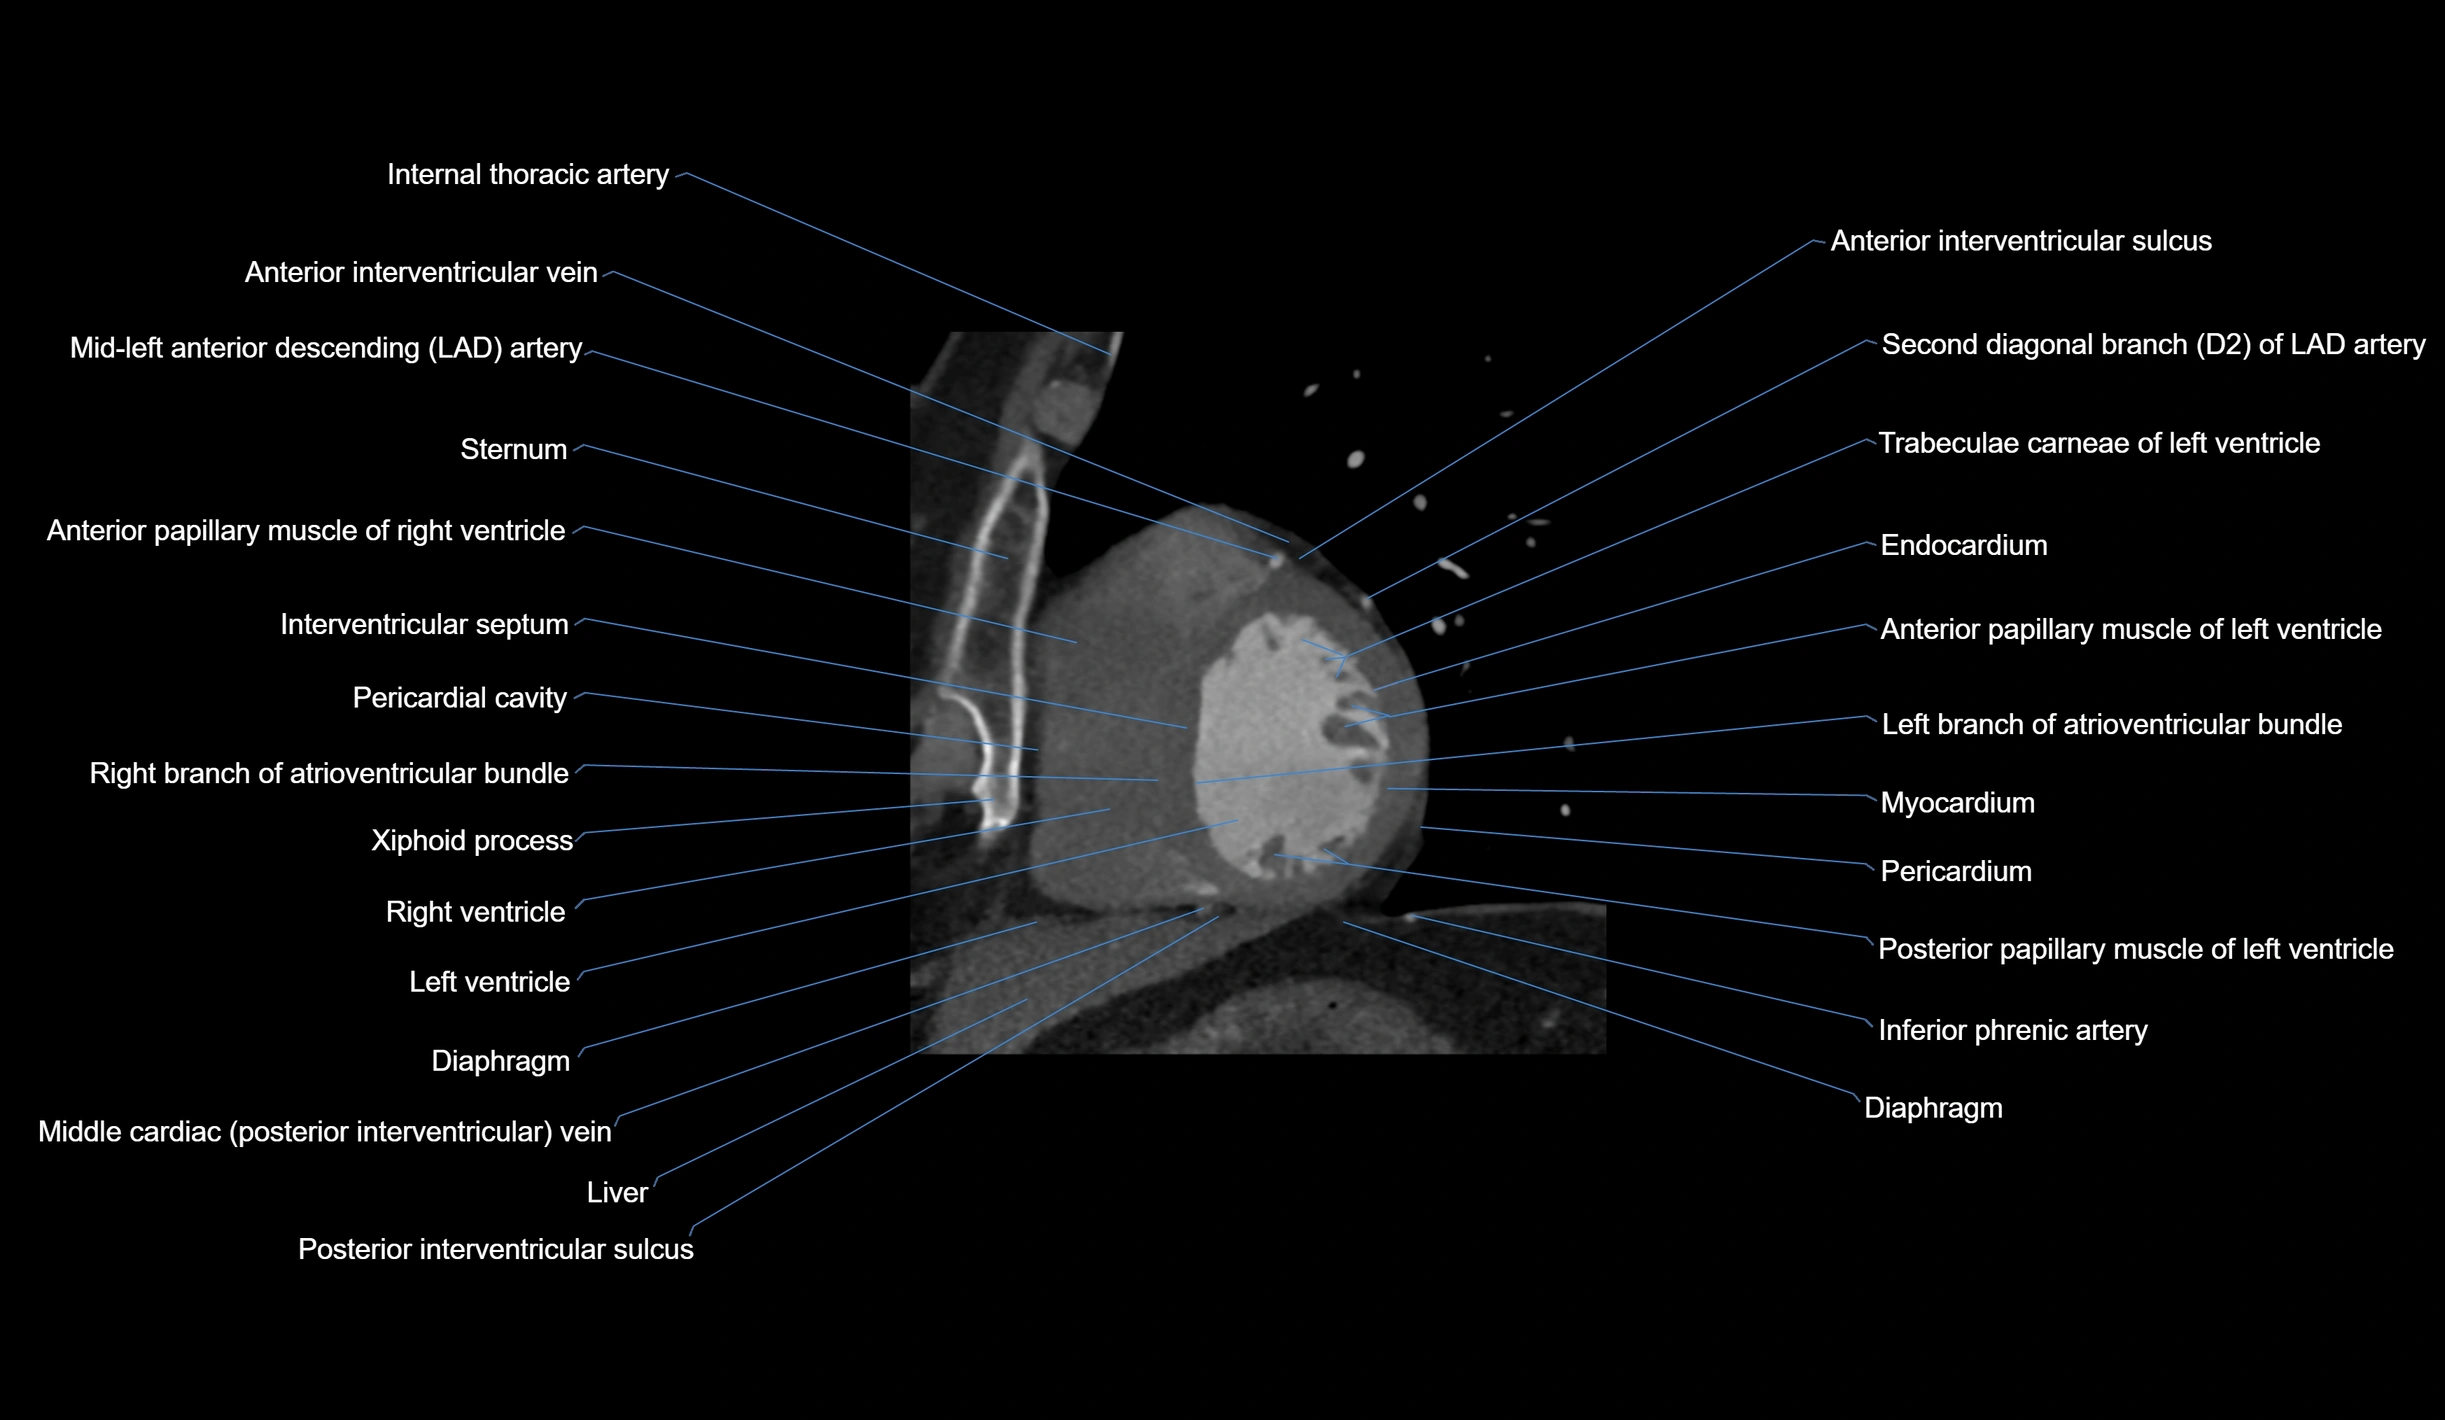

- Acute marginal artery (AM)

CT Appearance

CT Coronary Angiography (CCTA):

-

Best non-invasive modality for acute marginal artery visualization

Shows origin, course along the acute margin, and right ventricular branches

Detects stenosis, occlusion, calcified and non-calcified plaques, aneurysm, or anomalous course

Multiplanar reformats and 3D reconstructions help in pre-PCI and surgical planning

Critical for assessing right ventricular infarction risk in RCA disease

CT images